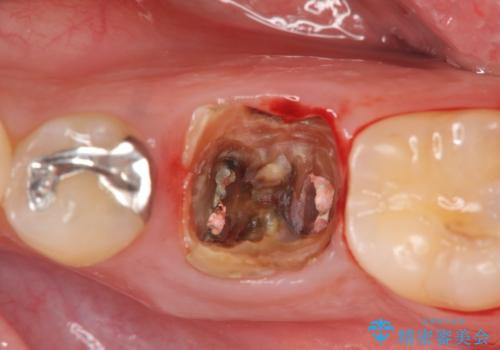

銀歯・レジンコアを除去したところ、薄い残存歯質に亀裂が入り、保存が難しい状況が認められました。

歯を残すことが難しい状況であることの説明、抜歯の提案を行い、抜歯後はブリッジ・入れ歯ではなくインプラント治療を希望されました。